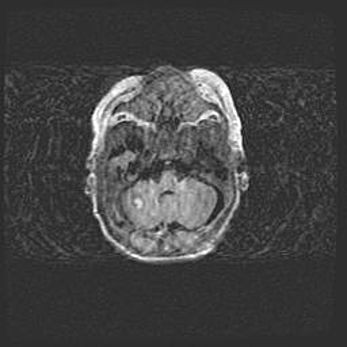

Наружная гидроцефалия с возможной атрофией височных областей.

Возраст: 28 дней

Вес: 3670 г

Пол: мужской

Окружность головы: 38 см

Срок гестации: 40 недель

Гидроцефалия головного мозга у новорожденных – это заболевание, которое характеризуется скоплением избыточного количества спинномозговой жидкости в желудочковой системе головного мозга в результате затруднения её перемещения от места выработки к месту поглощения в кровеносную систему или вследствие нарушения абсорбции. При открытой наружной форме гидроцефалии у новорожденных расширяются и переполняются субарахноидные пространства.

При нормотензивных  формах,  которые,  как  правило,  являются  следствием  перенесенных ишемических  повреждений  паренхимы  мозга,  возможно  сочетание микроцефалии  с нормотензивной гидроцефалией. В основе данных изменений лежит атрофия больших полушарий с преимущественной  локализацией  в  лобно-височных  областях.